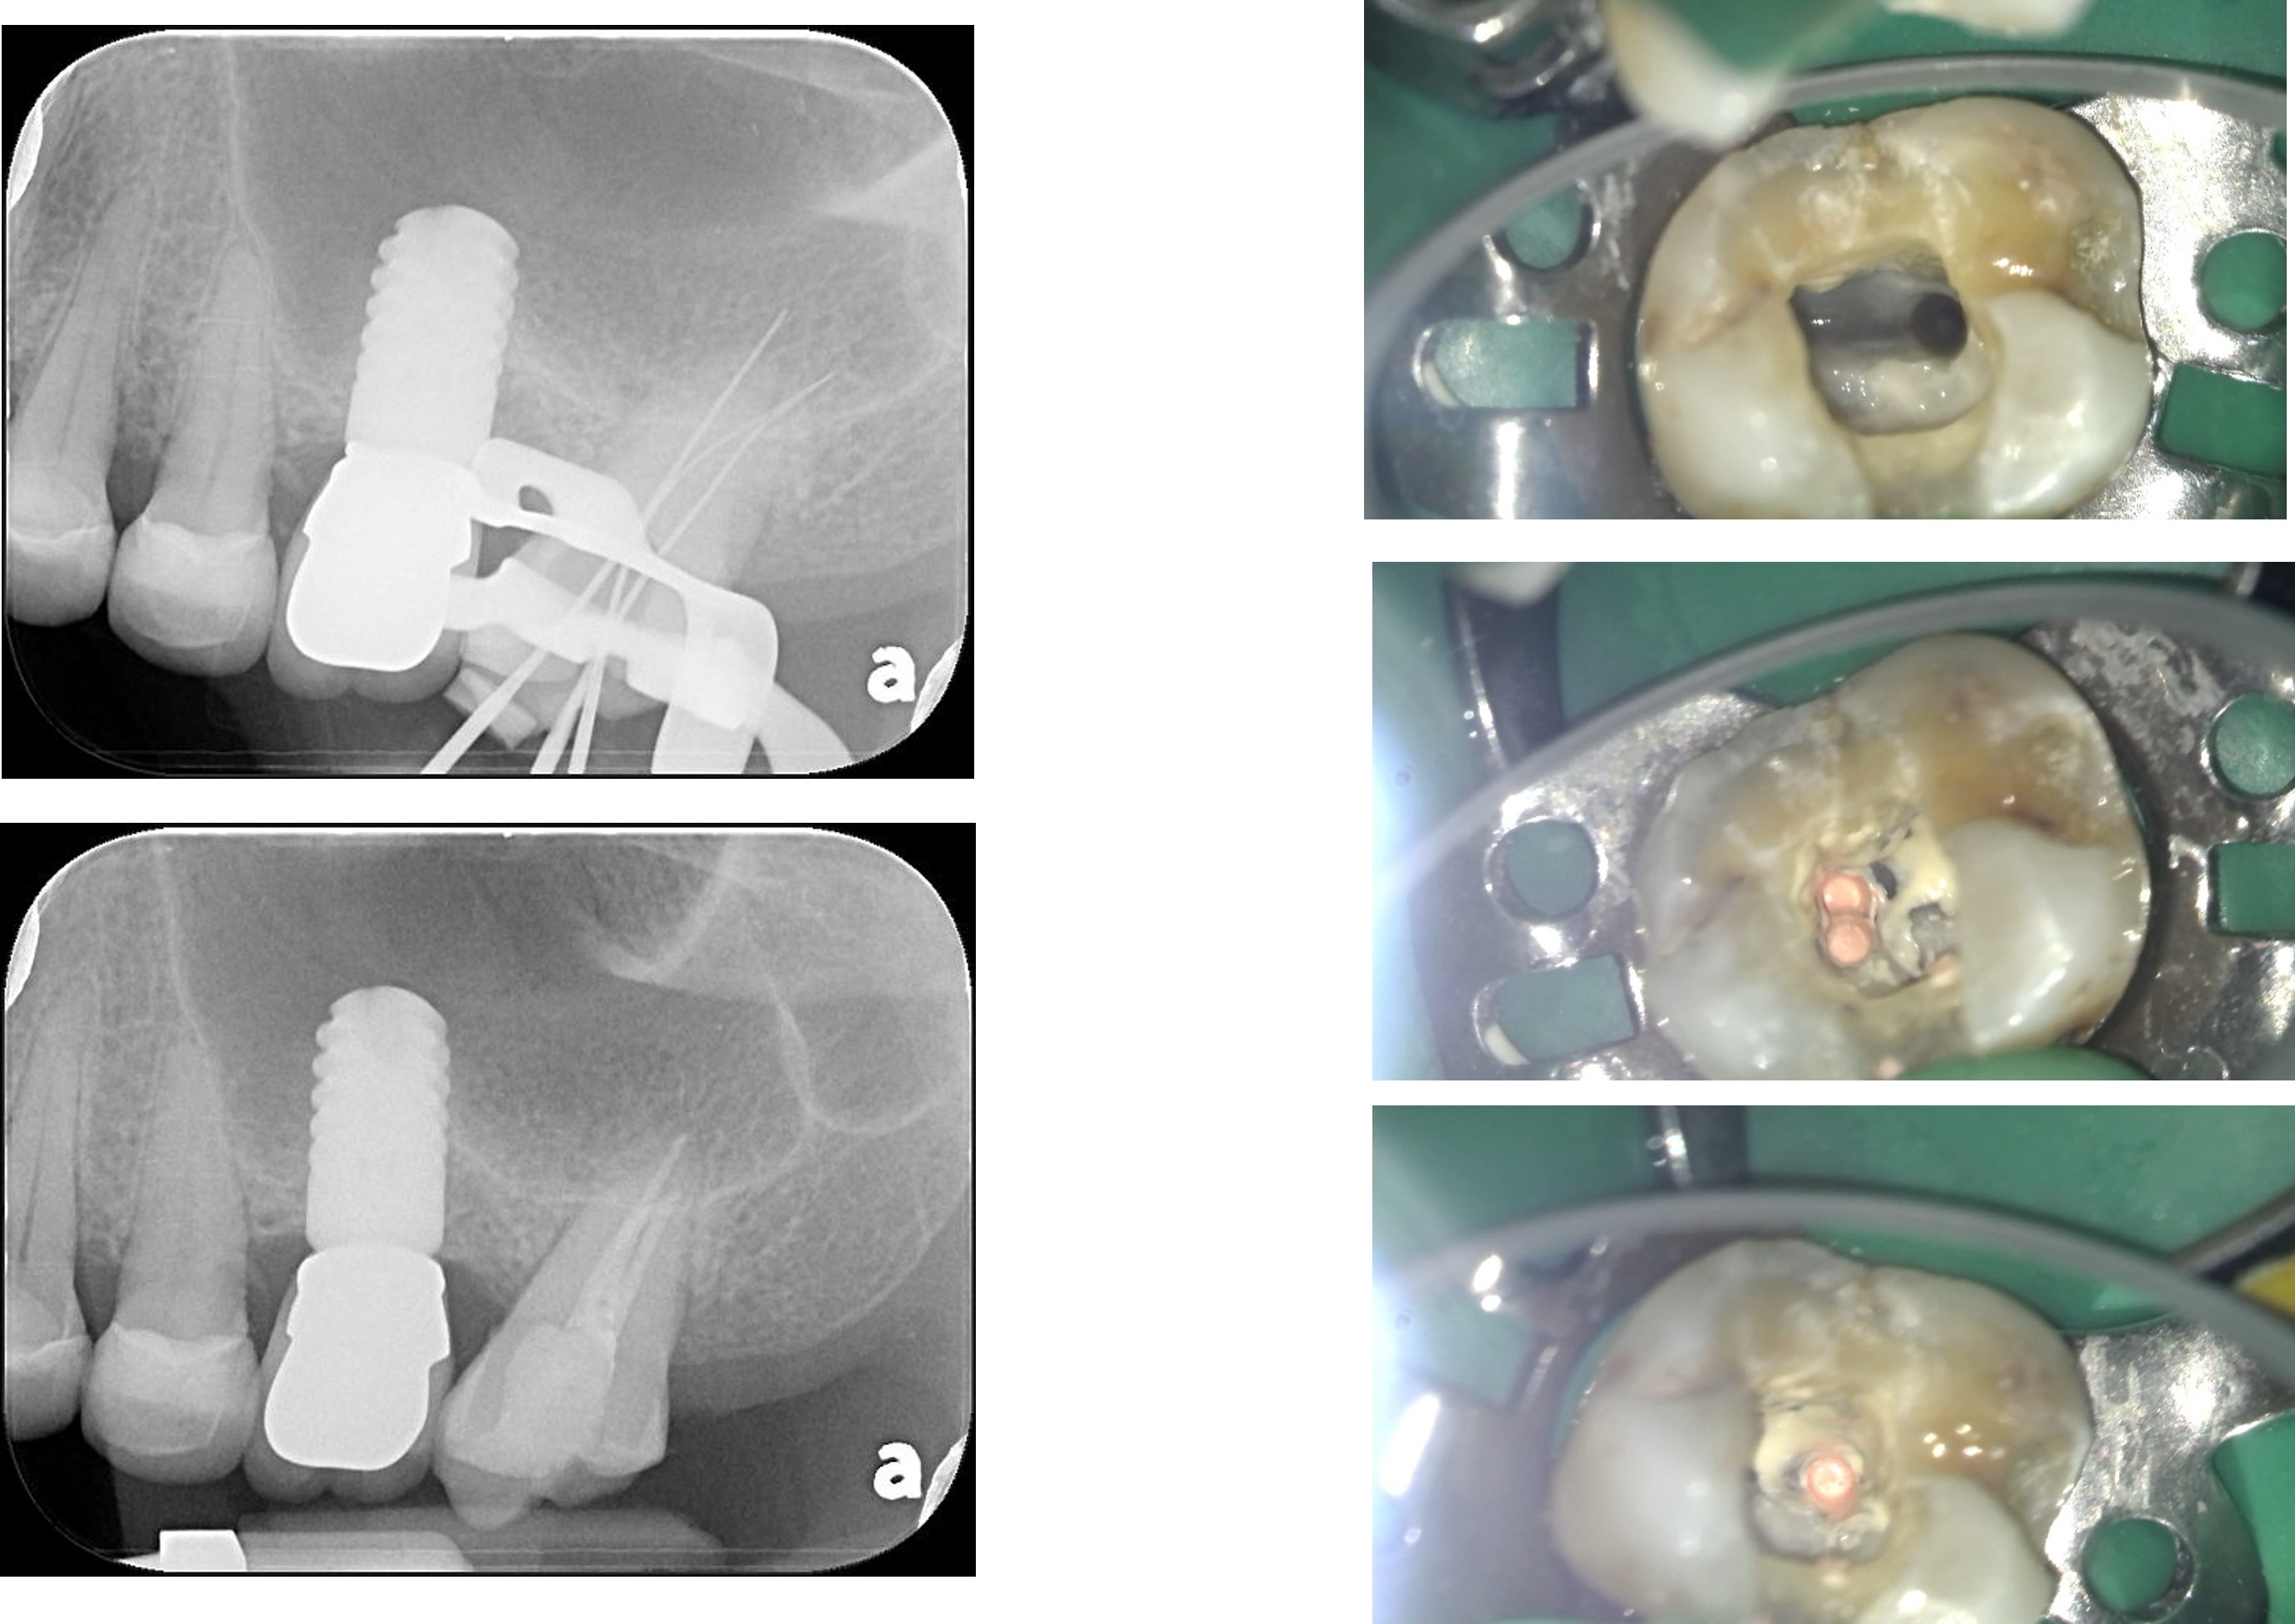

膺復前評估牙齦、牙齒狀態

上面弓、上咬合器

技師於咬合器製作全瓷冠

全鋯冠

治療後,牙周咬合良好

治療後,密合度良好

術前、術後比較